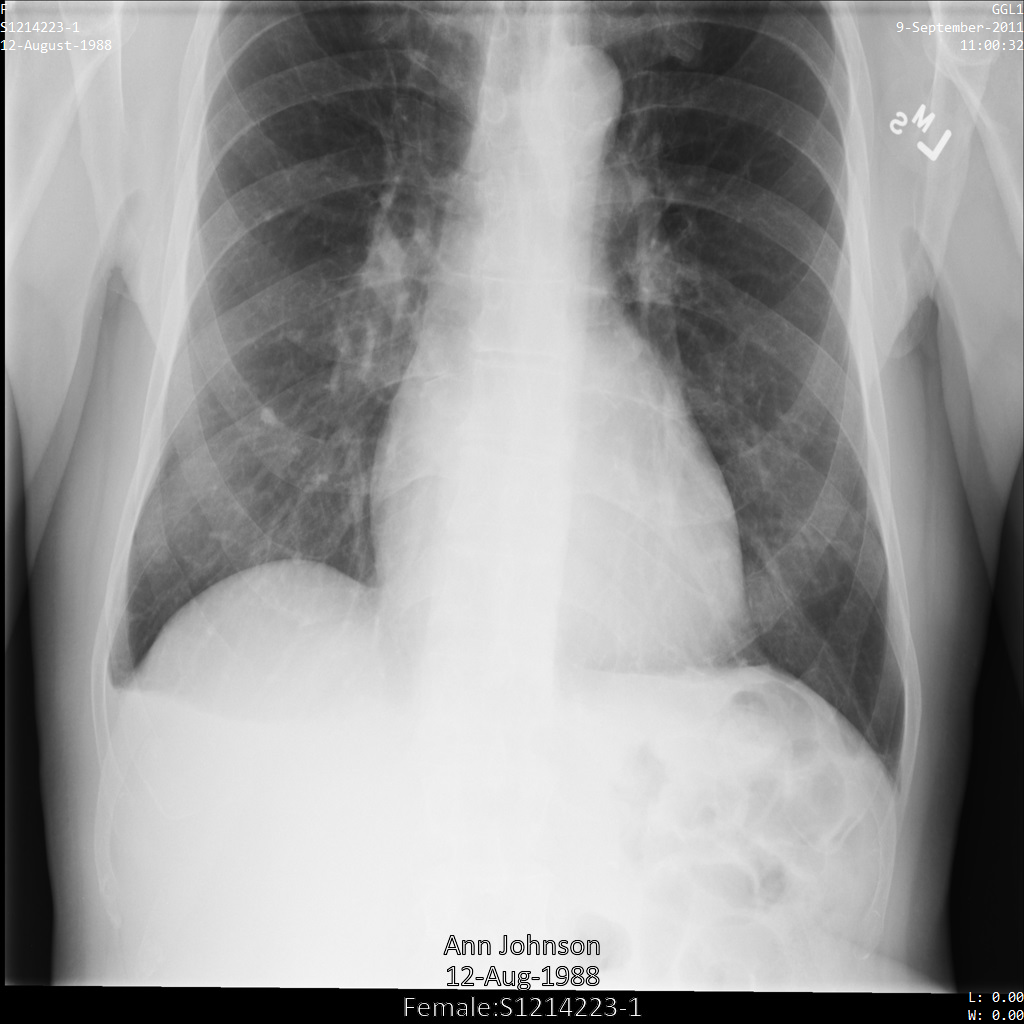

Une fois l'image envoyée à l'API Cloud Healthcare, elle apparaît comme suit. À l'exception des balises fournies dans la liste de suppression, seul PatientBirthDate est supprimé dans l'image, car il s'agit de la seule balise de la liste de suppressions qui correspond aux métadonnées visibles dans l'image.

Bien que le PatientBirthDate dans l'angle supérieur de l'image ait été masqué conformément à la configuration de la liste removelist, les données de santé protégées incrustées en bas de l'image sont conservées. Pour supprimer également le texte incrusté, consultez la section Masquer le texte incrusté dans les images.